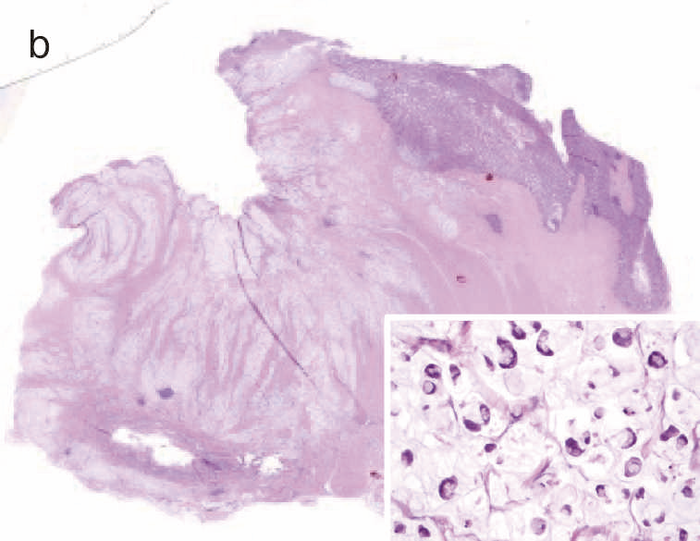

図28 CD関連進行直腸・肛門管癌(5型)の代表的な肉眼像・組織像

- 肉眼像:直腸・肛門管部に内腔狭窄を伴った5型腫瘍(矢印)を認める。

- 組織像(HE染色):組織学的には,壁内に浸潤している粘液癌を認める(inset:粘液癌の拡大像)。